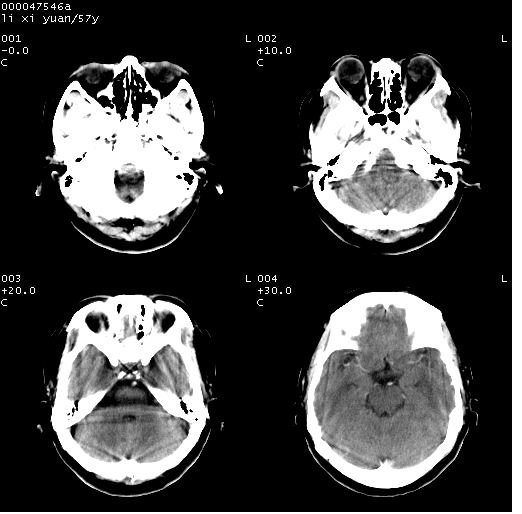

以下是引用zjzjr在2008-4-27 14:23:00的发言:[br]支持慢性炎性肉芽肿可能性大(增强效果较差).

以下是引用余辉在2008-4-27 14:02:00的发言:[br]病灶位于中央沟前方?位于额叶?高密度灶,灶周水肿不明显,病灶似沿脑沟走行,强化明显,局部层面呈现环状强化,考虑1脑表面血管性疾病,如血管瘤,血管扩张,灶内血栓形成,其次考虑肿瘤如脑膜瘤、转移瘤,胶母等

以下是引用形影不离在2008-4-27 14:13:00的发言:[br]考虑胶质瘤可能性大,不排除慢性炎性肉芽肿。建议mri检查。